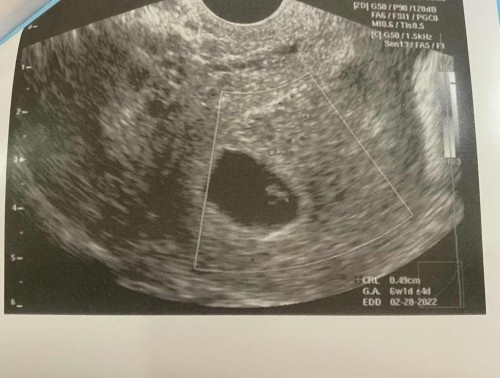

No heartbeat😢😭

Normal lang po ba sa 6 weeks and 1 day na wala pa heartbeat? Sabi kasi ni OB dapat meron na daw po heartbeat e tapos sabi pa niya if dinugo pumunta agad sa kanya kaya talagang nakakapa-isip po lalo.😭😢Super worried po talaga ako! Need advice po. Thank you so much po.🥺 May 8 (first day) po pala last mens ko. #2ndbaby #pregnancy #advicehelppls

Hi mamshie may ganyan po na minsan hindi agad na de-detect pero tama si OB dapat meron na sya HB kasi ako nalaman unang HB ni baby 6weeks and 2days. Meron din naman kami mga patient mga ganyan weeks walang HB pero nag wait pa ng mga 2weeks pag utz uli meron na HB basta tuloy lang ung vitamins and pampakapit kung may binigay si OB . Pero tama si OB once na ang spotting or dinugo ka mamshie need na talaga pumunta kay OB

aqo po kc 6weeks my heartbeat na...

sakin po 6 weeks ako nung nagpa trans v..and wla din heart beat..sac lang ang nakita.marami akong pagsubok na napagdaanan during my pregnancy..pro thanks god nkapanganak nako and 2 months na baby KO ngyon..wag lng po tayong mag alala early pregnancy pa po kc magka2heart beat din yan..😊😊ingat ka po lagi..

Magbasa paganyan din yung sakin be yung maliit pa tiyan ko sabi nang OB ko wla daw heartbeat yung baby ko . pero nung nagpa Ultrasound na ako Okay naman . may heartbeat naman si baby . ngayon 8 mons. na tummy ko. pagmaliit pa kasi di agad2 makikita heartbeat nya. keep praying lang be.

relax lng po and pray lng.. ako 6 weeks and 3 days na dapat yun peron nung nag pa TVS AKO 5weeks 1 day plng. bumalik ako after 2 weeks 8 weeks and 1day na and malakas na din heartbeat. Folic acid lng iniinom ko nun.. dasal lng po now im 16 weeks 3 days